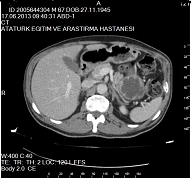

Bulgular: Fizik muayenesinde; TA: 120/80mm/Hg, NB: 88 atım/dk, yuzunde rozasea mevcuttu, sistem muayenesi doğaldı. Laboratuvar analizinde; TSH:1,2mU/L(0,55-4-78), sT3:3,24ng/L (2,3-4,2), sT4:1,26ng/dl(0,89-1,76), Hb:12g/dL(12-15,6), ferritin:6 mikrogram/L(10-291), aTG:269,9IU/mL(<1,3), aTPO:389U/mL(<60), glukoz:86mg/dl(70-99) idi. Hasta levotiroksin 100mcg tedavisi alıyordu. Klinik takibinde taşikardisi nedeni ile ilac dozu duşuruldu, demir eksikliği anemisi nedeni ile replasman tedavisi aldı. Taşikardisi nedeni ile kardiyoloji bolumune yonlendirilen hastaya ekokardiyografi(EKO) planlandığı ancak hastanın yaptırmadığı oğrenildi. Aclık ve tokluk hipoglisemileri olan hastaya mixed meal testi yapıldı, test sırasında hipoglisemik değeri olmadı, uzamış aclık testi planlandı ancak yatış kabul etmedi. Pankreas MR’ında, sol atrium icerisinde 38x36mm boyutlarında T1A’de hipo, T2AG’de hiperintens, IVKM enjeksiyonu sonrası yapılan dinamik incelemede kontrastlanmayan lezyon goruldu. Pankreas parankim intensitesi homojen olduğu saptandı, belirgin kitle lezyonu gorulmedi. EKO’sunda ejeksiyon fraksiyonu: %60, sol atrium icerisinde 4,3x3,3cm, duzgun sınırlı yuvarlak şekilde, interatrial septuma sap ile tutunan ve septumu sağa deviye eden icerde yer yer kalsifikasyon odakları iceren miksoma uyumlu kitle izlendi. Hasta sol atriyal kitle nedeniyle opere oldu. Patoloji sonucu kardiyak miksoma ile uyumlu geldi. Hastanın Karney kompleksi acısından tetkiklerinde; 1mg DST kortizol baskılı, Glukoz-GH supresyon testi GH <0,05μg/L, genetik test calışılamadı.